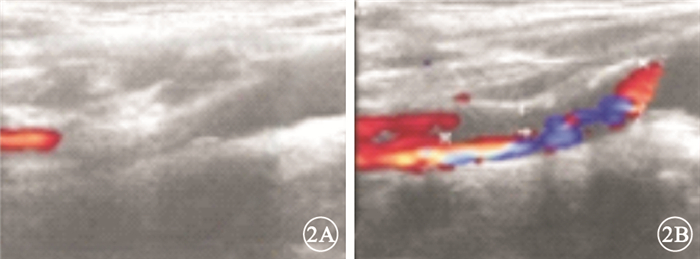

圖1

左眼彩色眼底像。視網膜顳上動脈及靜脈管徑變細,顳上支動脈主干分叉處可見2個節段狀黃白色反光灶,其遠端小分支動脈閉塞,顳上動脈分布區視網膜顏色灰白,顳下動脈黃斑分支末端可見1個點狀黃白色反光灶

圖1

左眼彩色眼底像。視網膜顳上動脈及靜脈管徑變細,顳上支動脈主干分叉處可見2個節段狀黃白色反光灶,其遠端小分支動脈閉塞,顳上動脈分布區視網膜顏色灰白,顳下動脈黃斑分支末端可見1個點狀黃白色反光灶

圖1

左眼彩色眼底像。視網膜顳上動脈及靜脈管徑變細,顳上支動脈主干分叉處可見2個節段狀黃白色反光灶,其遠端小分支動脈閉塞,顳上動脈分布區視網膜顏色灰白,顳下動脈黃斑分支末端可見1個點狀黃白色反光灶

圖1

左眼彩色眼底像。視網膜顳上動脈及靜脈管徑變細,顳上支動脈主干分叉處可見2個節段狀黃白色反光灶,其遠端小分支動脈閉塞,顳上動脈分布區視網膜顏色灰白,顳下動脈黃斑分支末端可見1個點狀黃白色反光灶